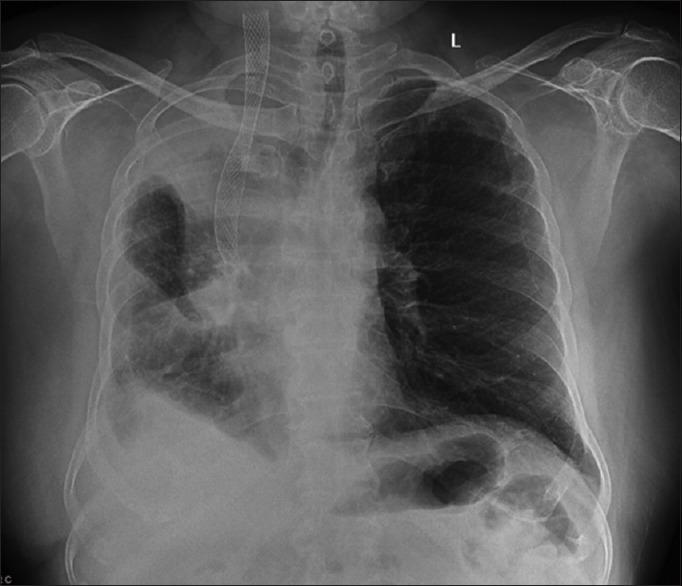

The treatment of malignant superior vena cava syndrome (SVCS) revolves around radiotherapy and chemotherapy to relieve symptoms with surgery being ruled out due to the advanced stage of malignancy. Primary placement of endovascular stent for palliation of malignant SVCS is not commonly reported in the literature. Here, we present two cases of malignant superior vena cava syndrome with successful relief of symptoms after the placement of endo vascular stent.

恶性上腔静脉综合征(SVCS)的治疗主要围绕放疗和化疗以缓解症状,由于恶性肿瘤处于晚期,手术被排除在外。文献中较少报道通过血管内支架置入术来缓解恶性SVCS的症状。在此,我们报告两例恶性上腔静脉综合征患者,在置入血管内支架后症状成功缓解。